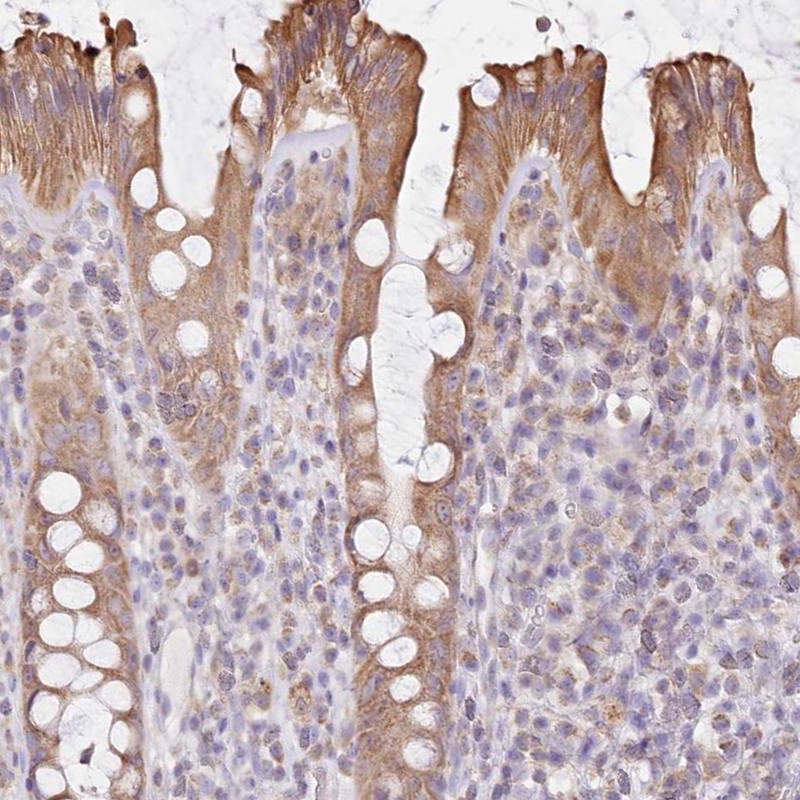

Immunohistochemical staining of human rectum shows moderate cytoplasmic positivity in glandular cells.